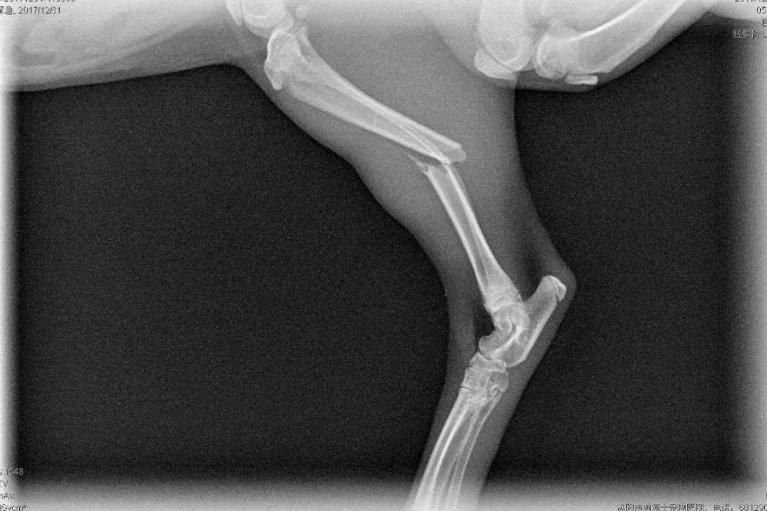

02:猫咪常见骨折部位有哪些?

(一)

四肢骨折是猫咪最常见的骨折。

绝大部分由外伤导致,

也是冬季在家最容易出现的猫咪伤病之一,

无论是从高处跌落,

还是被门挤到爪子,

甚或是猫猫之间打架斗殴都可能会把骨头折断。

一些幼龄猫或体态过于肥胖的猫的骨质更脆弱,

或承受的压力更大,也更容易出现四肢骨折。

轻微的骨折通过观察和触诊很难确诊,

建议铲屎官带猫咪进行X光片检查。